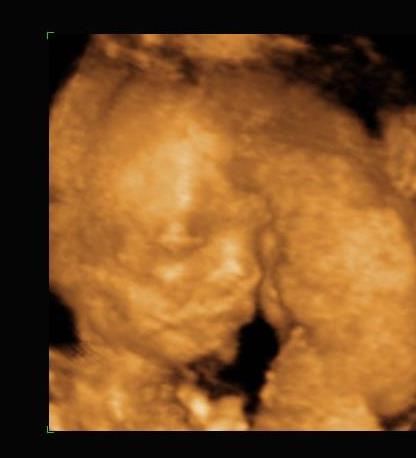

rólunk:

megvolt a 4D a Kárpát utcában, babát rendben találta az uh-s néni.

sajna nagyon elbújt a baba, így nem sok képet tudott csinálni róla, de kettőt azért felteszek.

a kisfiús szülők táborát erősítjük. :-)

Kép